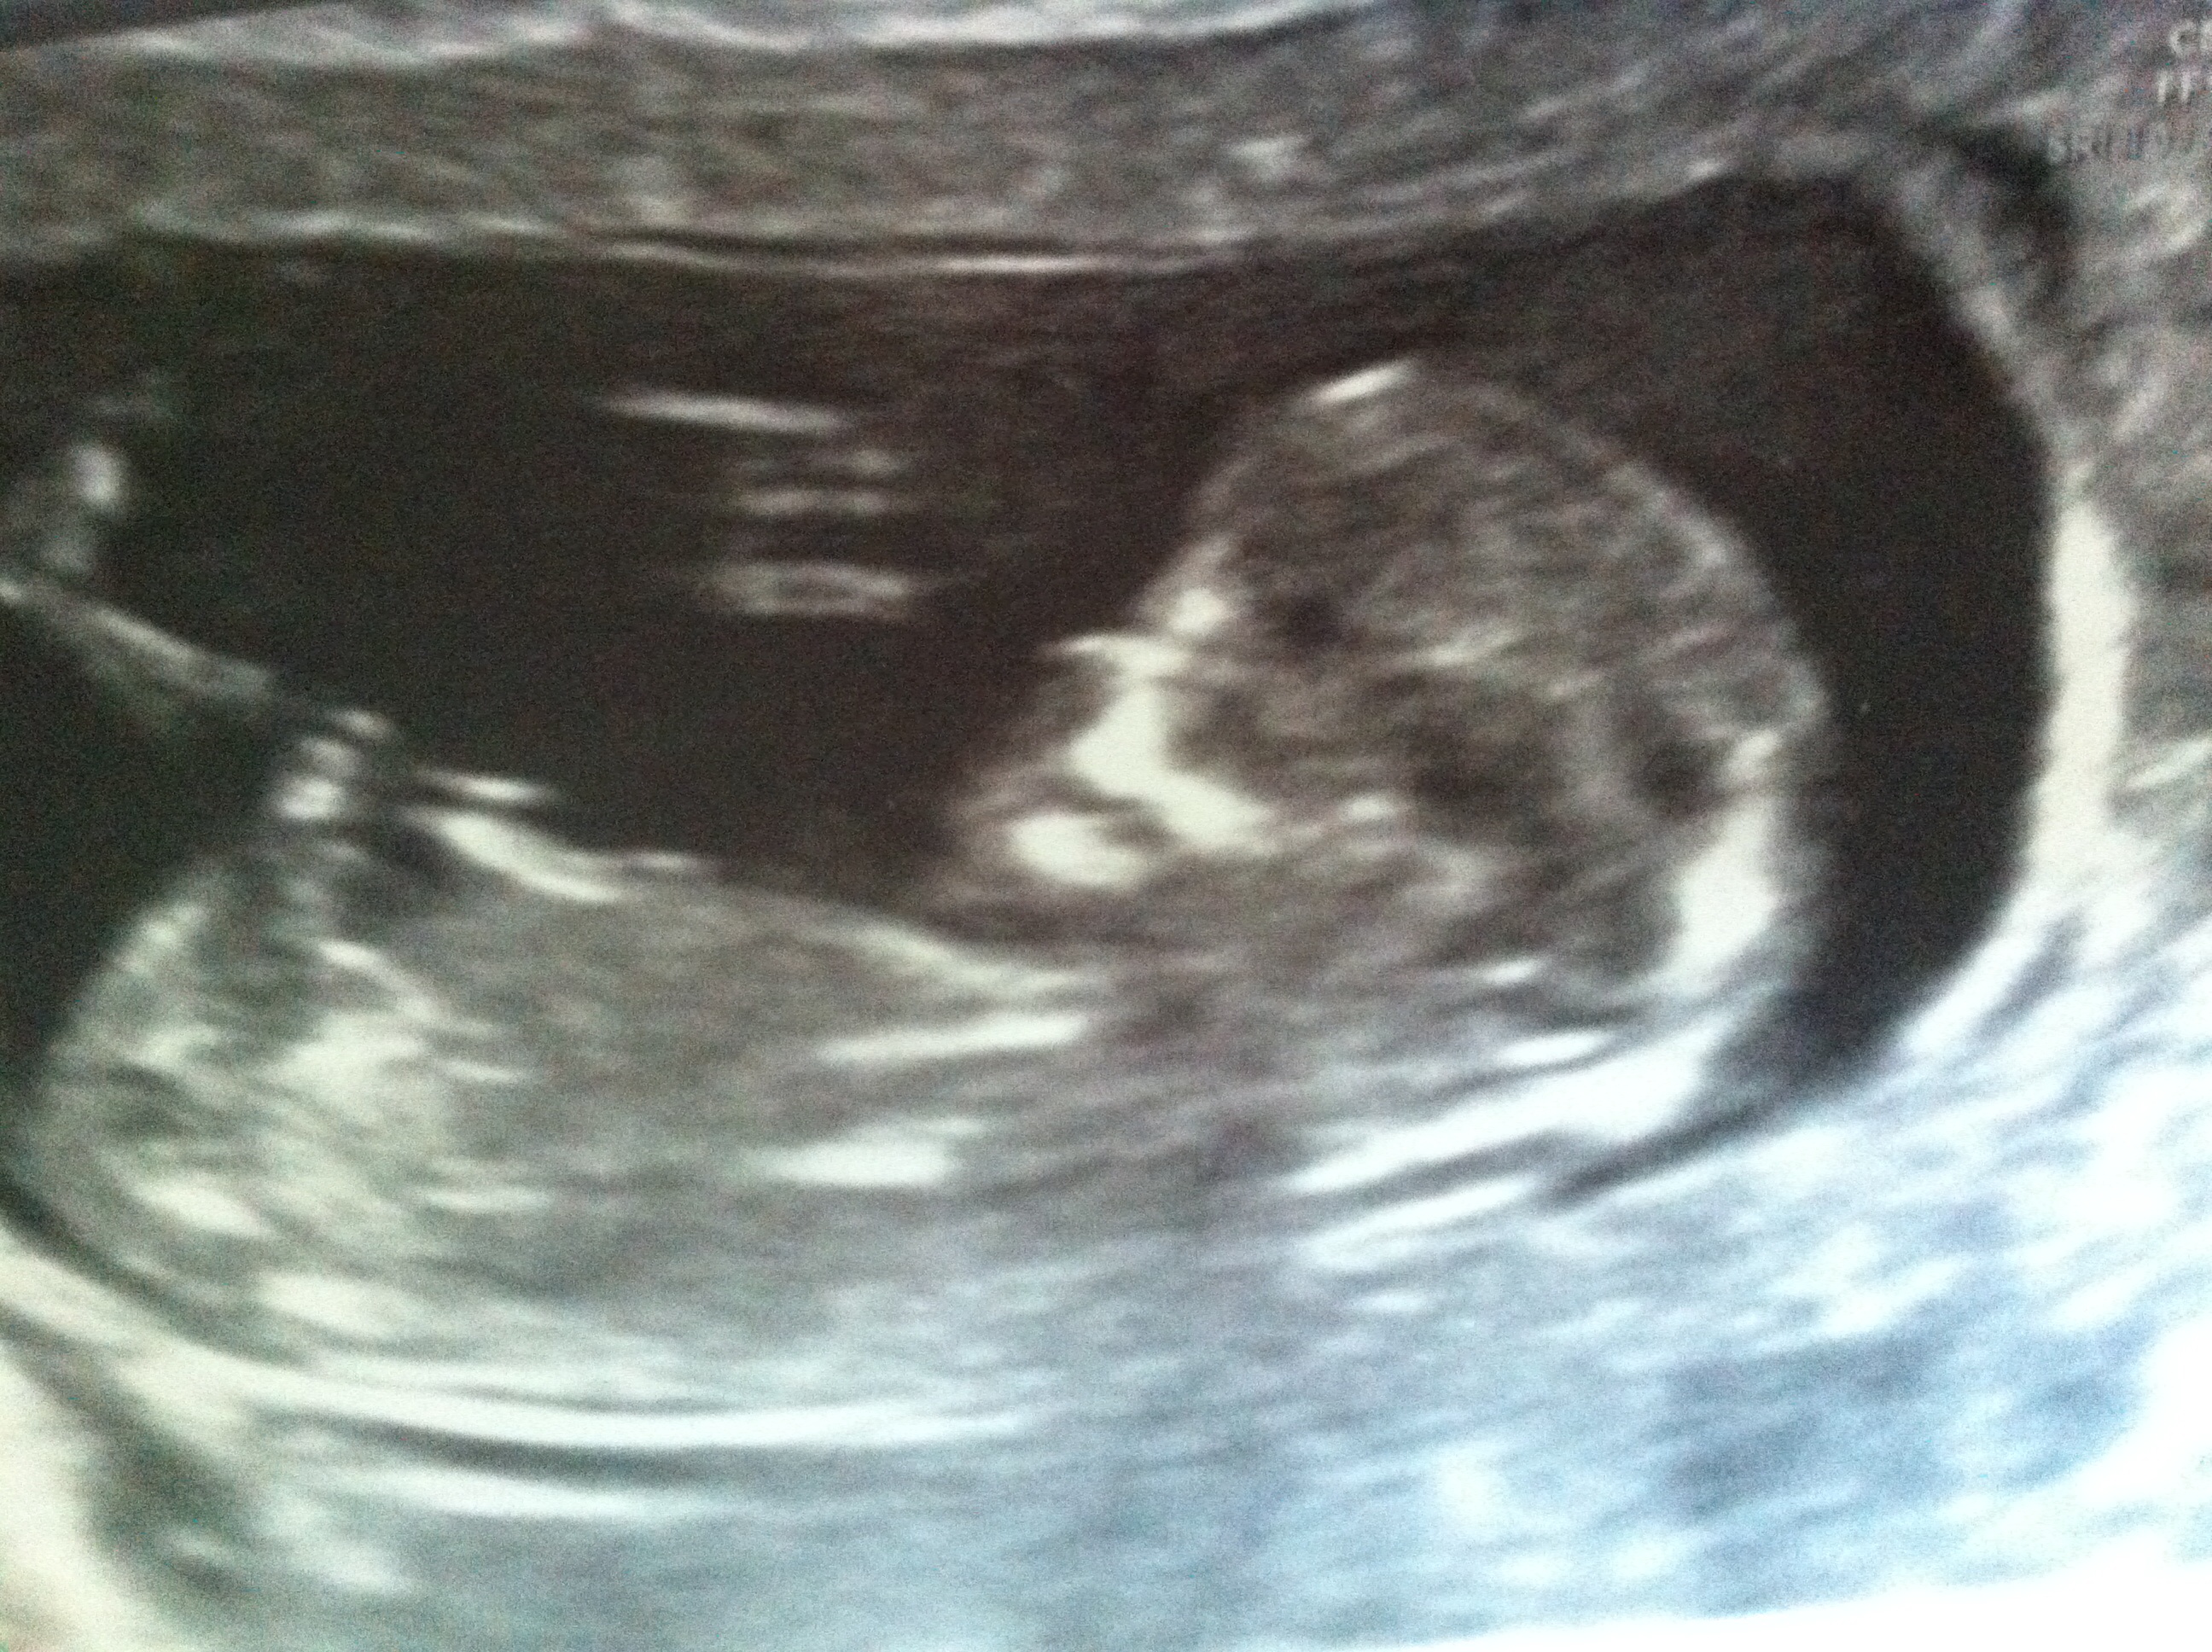

Attachment 18795 What do you all think x

Sorry I can't see a nub there but I think skull looks boyish. x

no nub

agreed no nub :(